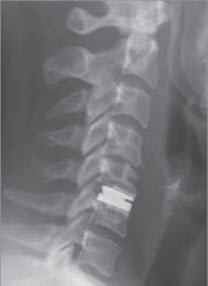

Da die entfernte Bandscheibe einen «Hohlraum» zurücklässt, wird dieser mit einem Platzhalter ausgefüllt. Dies kann mit eigenem Knochen (Beckenkamm) oder mit Fremdmaterial (sog. Cage) erfolgen. Damit erreicht man gleichzeitig eine Verblockung der Wirbelkörper, die mit einer Platte gesichert werden kann. Diese Versteifung beeinträchtigt die Gesamtbeweglichkeit der Halswirbelsäule kaum. Gelegentlich wird anstelle der Verblockung die Bandscheibe durch eine bewegliche Prothese ersetzt.

Gegen Verkrampfungen der Genick- und Schultermuskulatur helfen warme Duschen und Bäder, warme Heublumen-Packungen oder auch die einfache warme Bettflasche. Die Schonungszeit beträgt sechs Wochen. Schmerzmittel sind meist nach wenigen Tagen nur noch selten oder sporadisch notwendig. Nach Versteifung ist die Behandlung die gleiche wie jene ohne Versteifung. Die Knochen-Entnahmestelle am Beckenkamm kann für einige Tage zum Gebrauch einfacher Schmerzmittel zwingen. Rund sechs Wochen nach der Operation wird die Kontrolle mit einfachen Röntgenbildern der Halswirbelsäule durchgeführt.